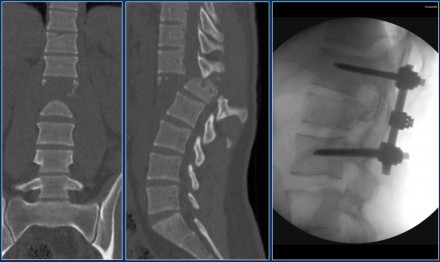

This is an interesting case since non-surgical management was initially attempted in this patient.

However when we classify according to the TLICS-score, we give 4 points for the morphology and 3 points for the PLC.

Assuming the neurological exam was normal, this patient would still get 7 points.

Unfortunately, but not unexpectedly, conservative management failed with near-dislocation.

Finally a posterior spondylodesis was performed.